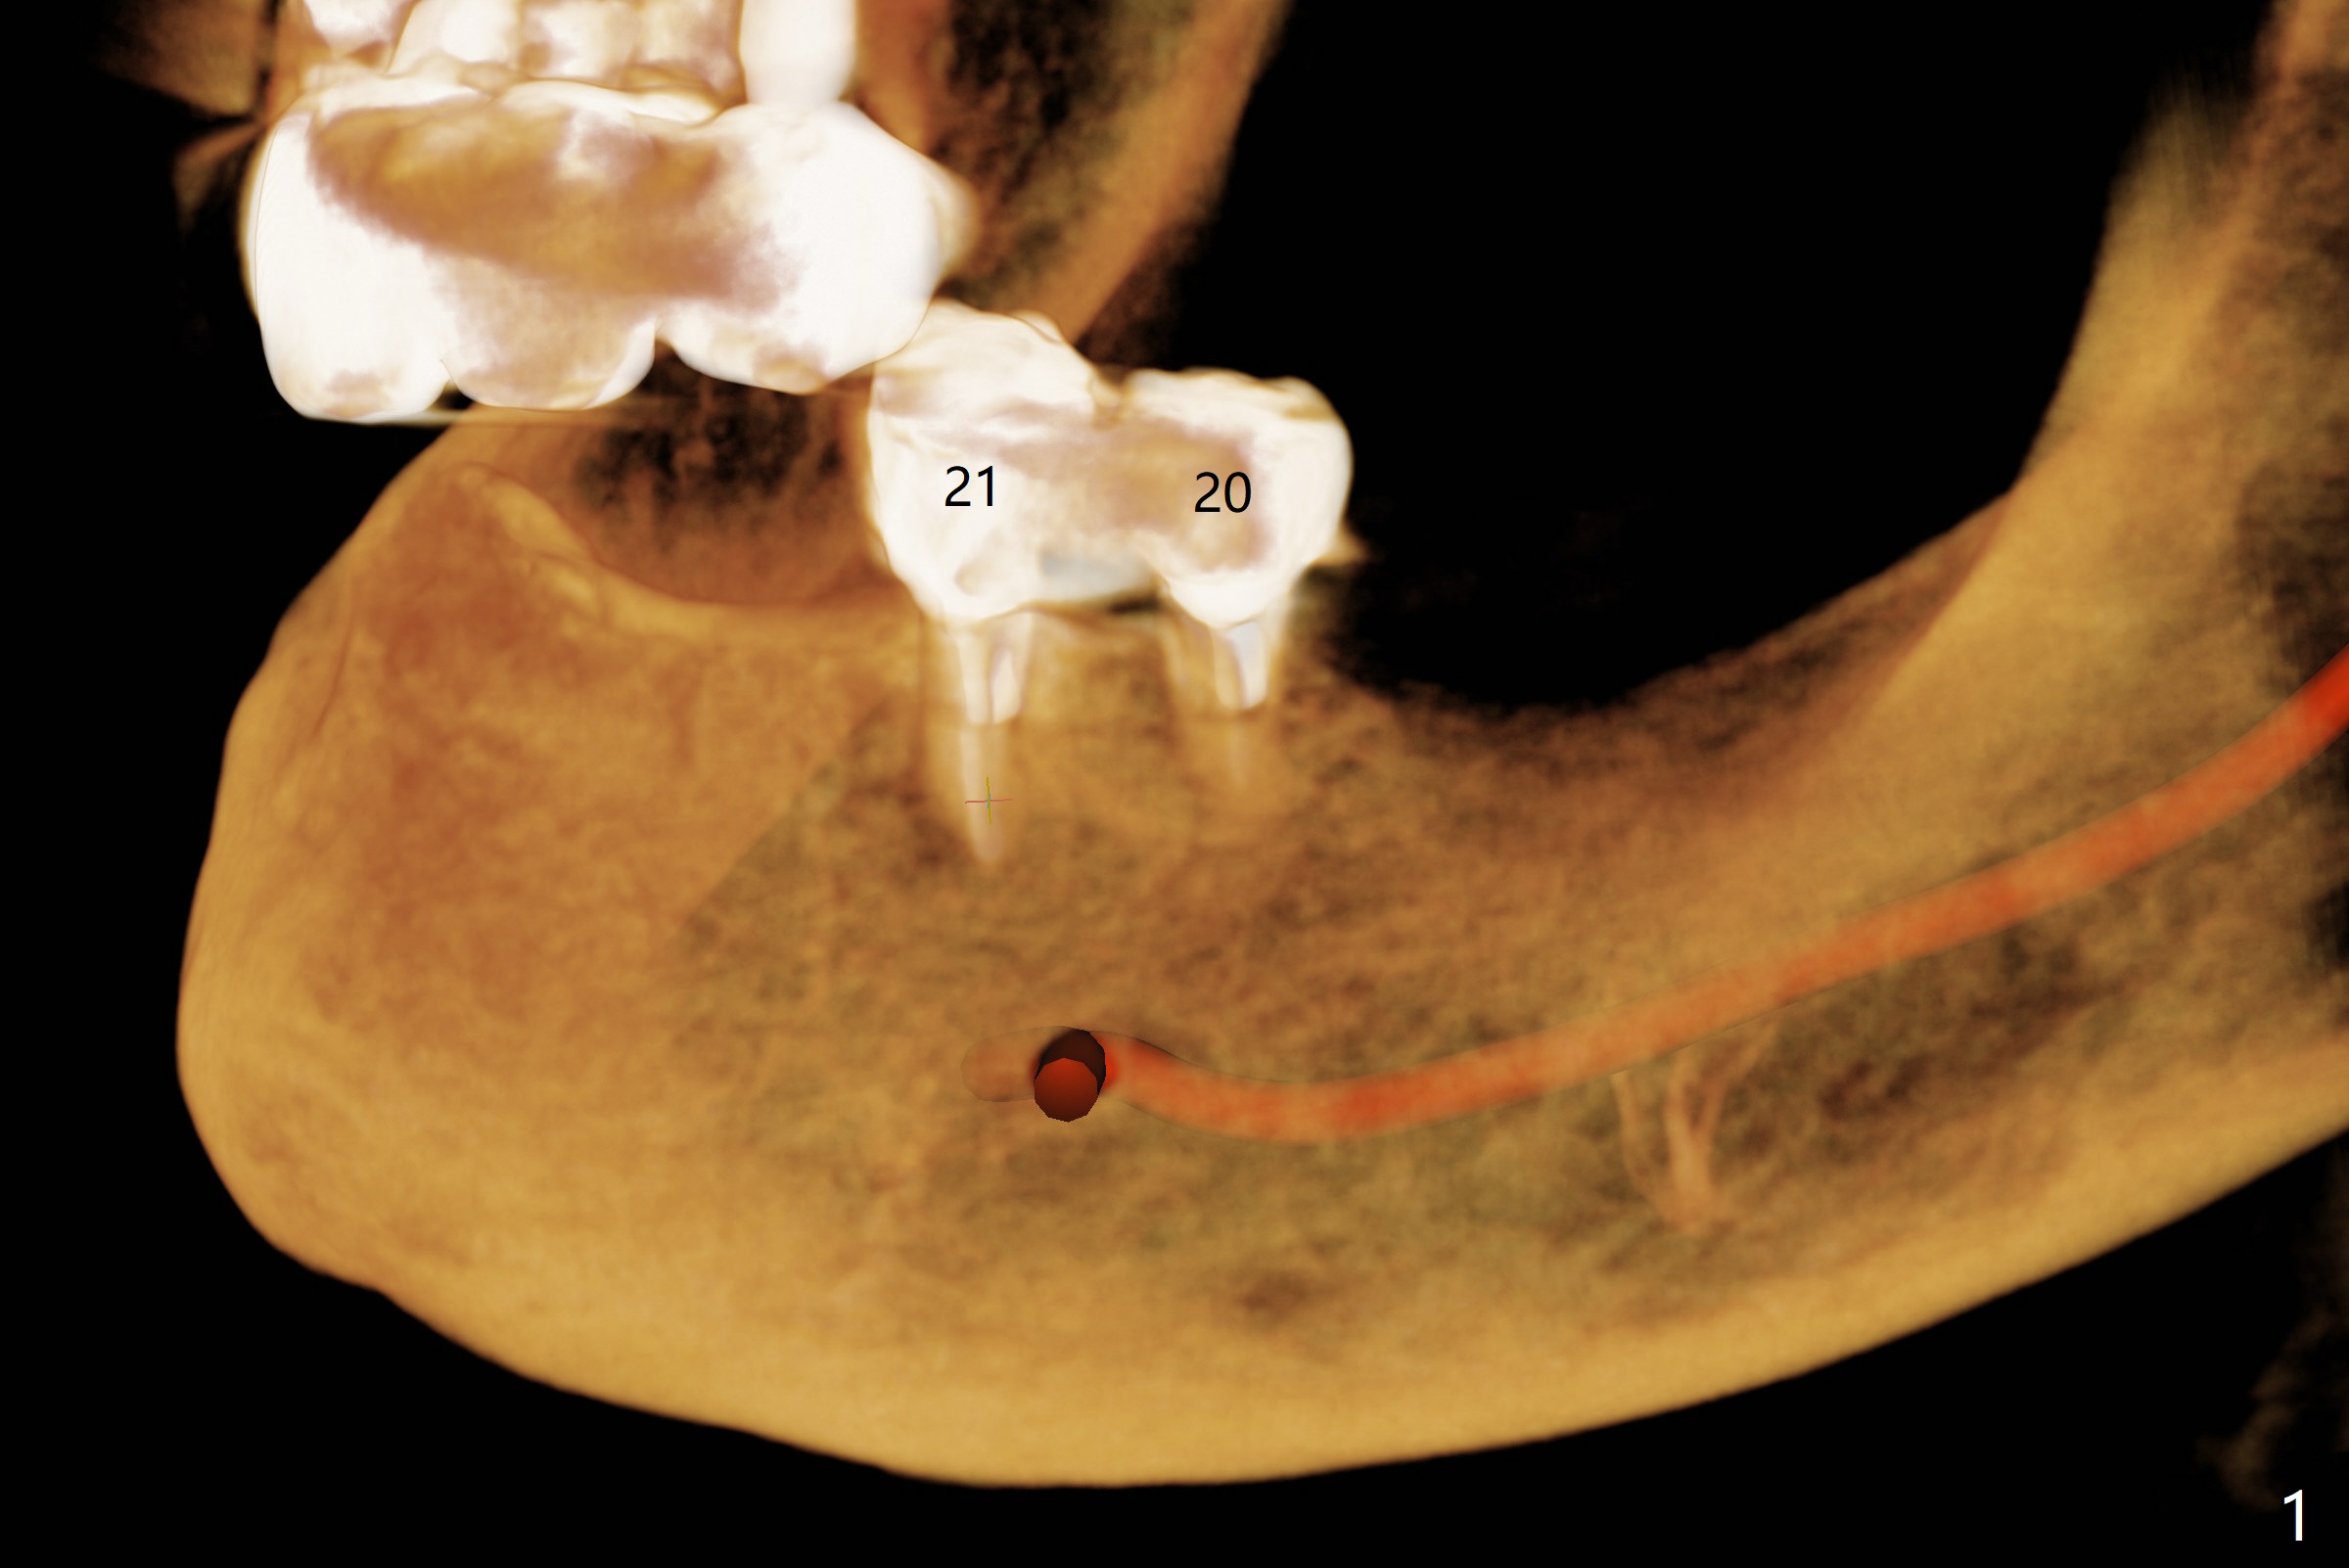

When the patient returns 4 months post #26 implant 2nd placement, the fractured crowns at #20 and 21 are loose. The roots are not difficult to remove. Since the bone height is limited (Fig.1,2), immediate implants are 3.8x8 and 3.8x10 mm, respectively with insertion torque >30 Ncm. Ball abutments (3.9x2 mm) are placed at #20 and 21; the existing lower RPD is soft relined using #26 1-piecee implant as an abutment. The retention of the RPD improves. Another implant will be placed in the lower right quadrant. One month 10 days postop, the ball abutment at #21 seems to be low (Fig.6). It is removed after laser gingivectomy and replaced with a ball abutment with 4 mm cuff. When the patient closes without RPDs, the 1-piece implant at #26 is barely buccal to the upper ridge (Fig.7). It appears that crowns have to be fabricated at #20,21,26 and 27 prior to refabrication of the lower RPD.